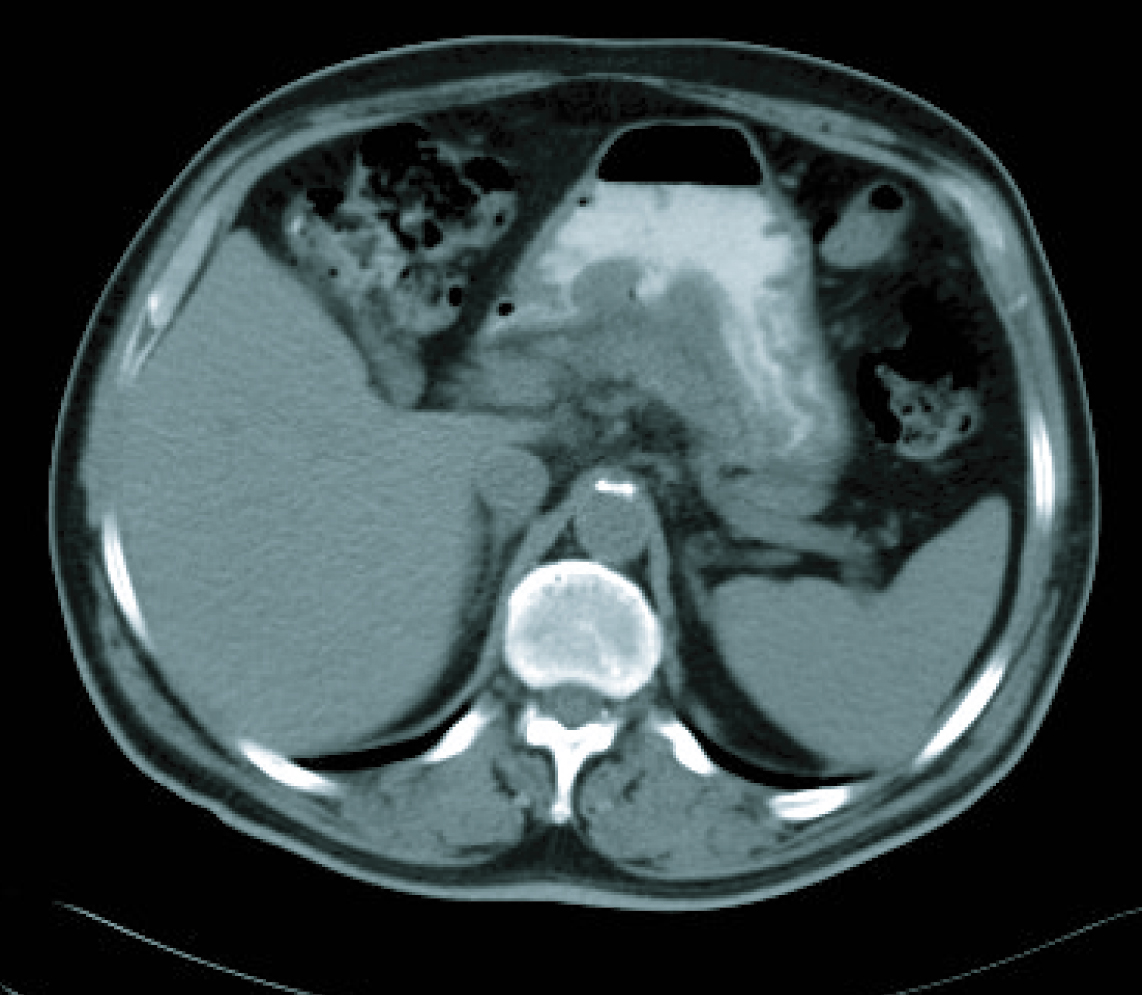

In a radiological re-assessment after the third treatment cycle, a significant reduction of adenopathies and gastric wall thickening was observed. Thus the response was re-evaluated as a partial remission, and after continuing for three more cycles of treatment, the radiological re-assessment maintained the same response (Fig. 3, 4). After the sixth treatment cycle was completed, the follow-up began. The patient continued with periodic evaluations, maintaining a good general state (ECOG 0) and a 14 kg weight gain since diagnosis. Follow-up CT scans showed that the radiological remission was maintained, and that there was a reduction of gastric wall thickening and normalisation of remote lymph nodes.

![]() Click for large image | Figure 3. CT imaging after 6 cicles. |

![]() Click for large image | Figure 4. CT imaging after 6 cicles. |